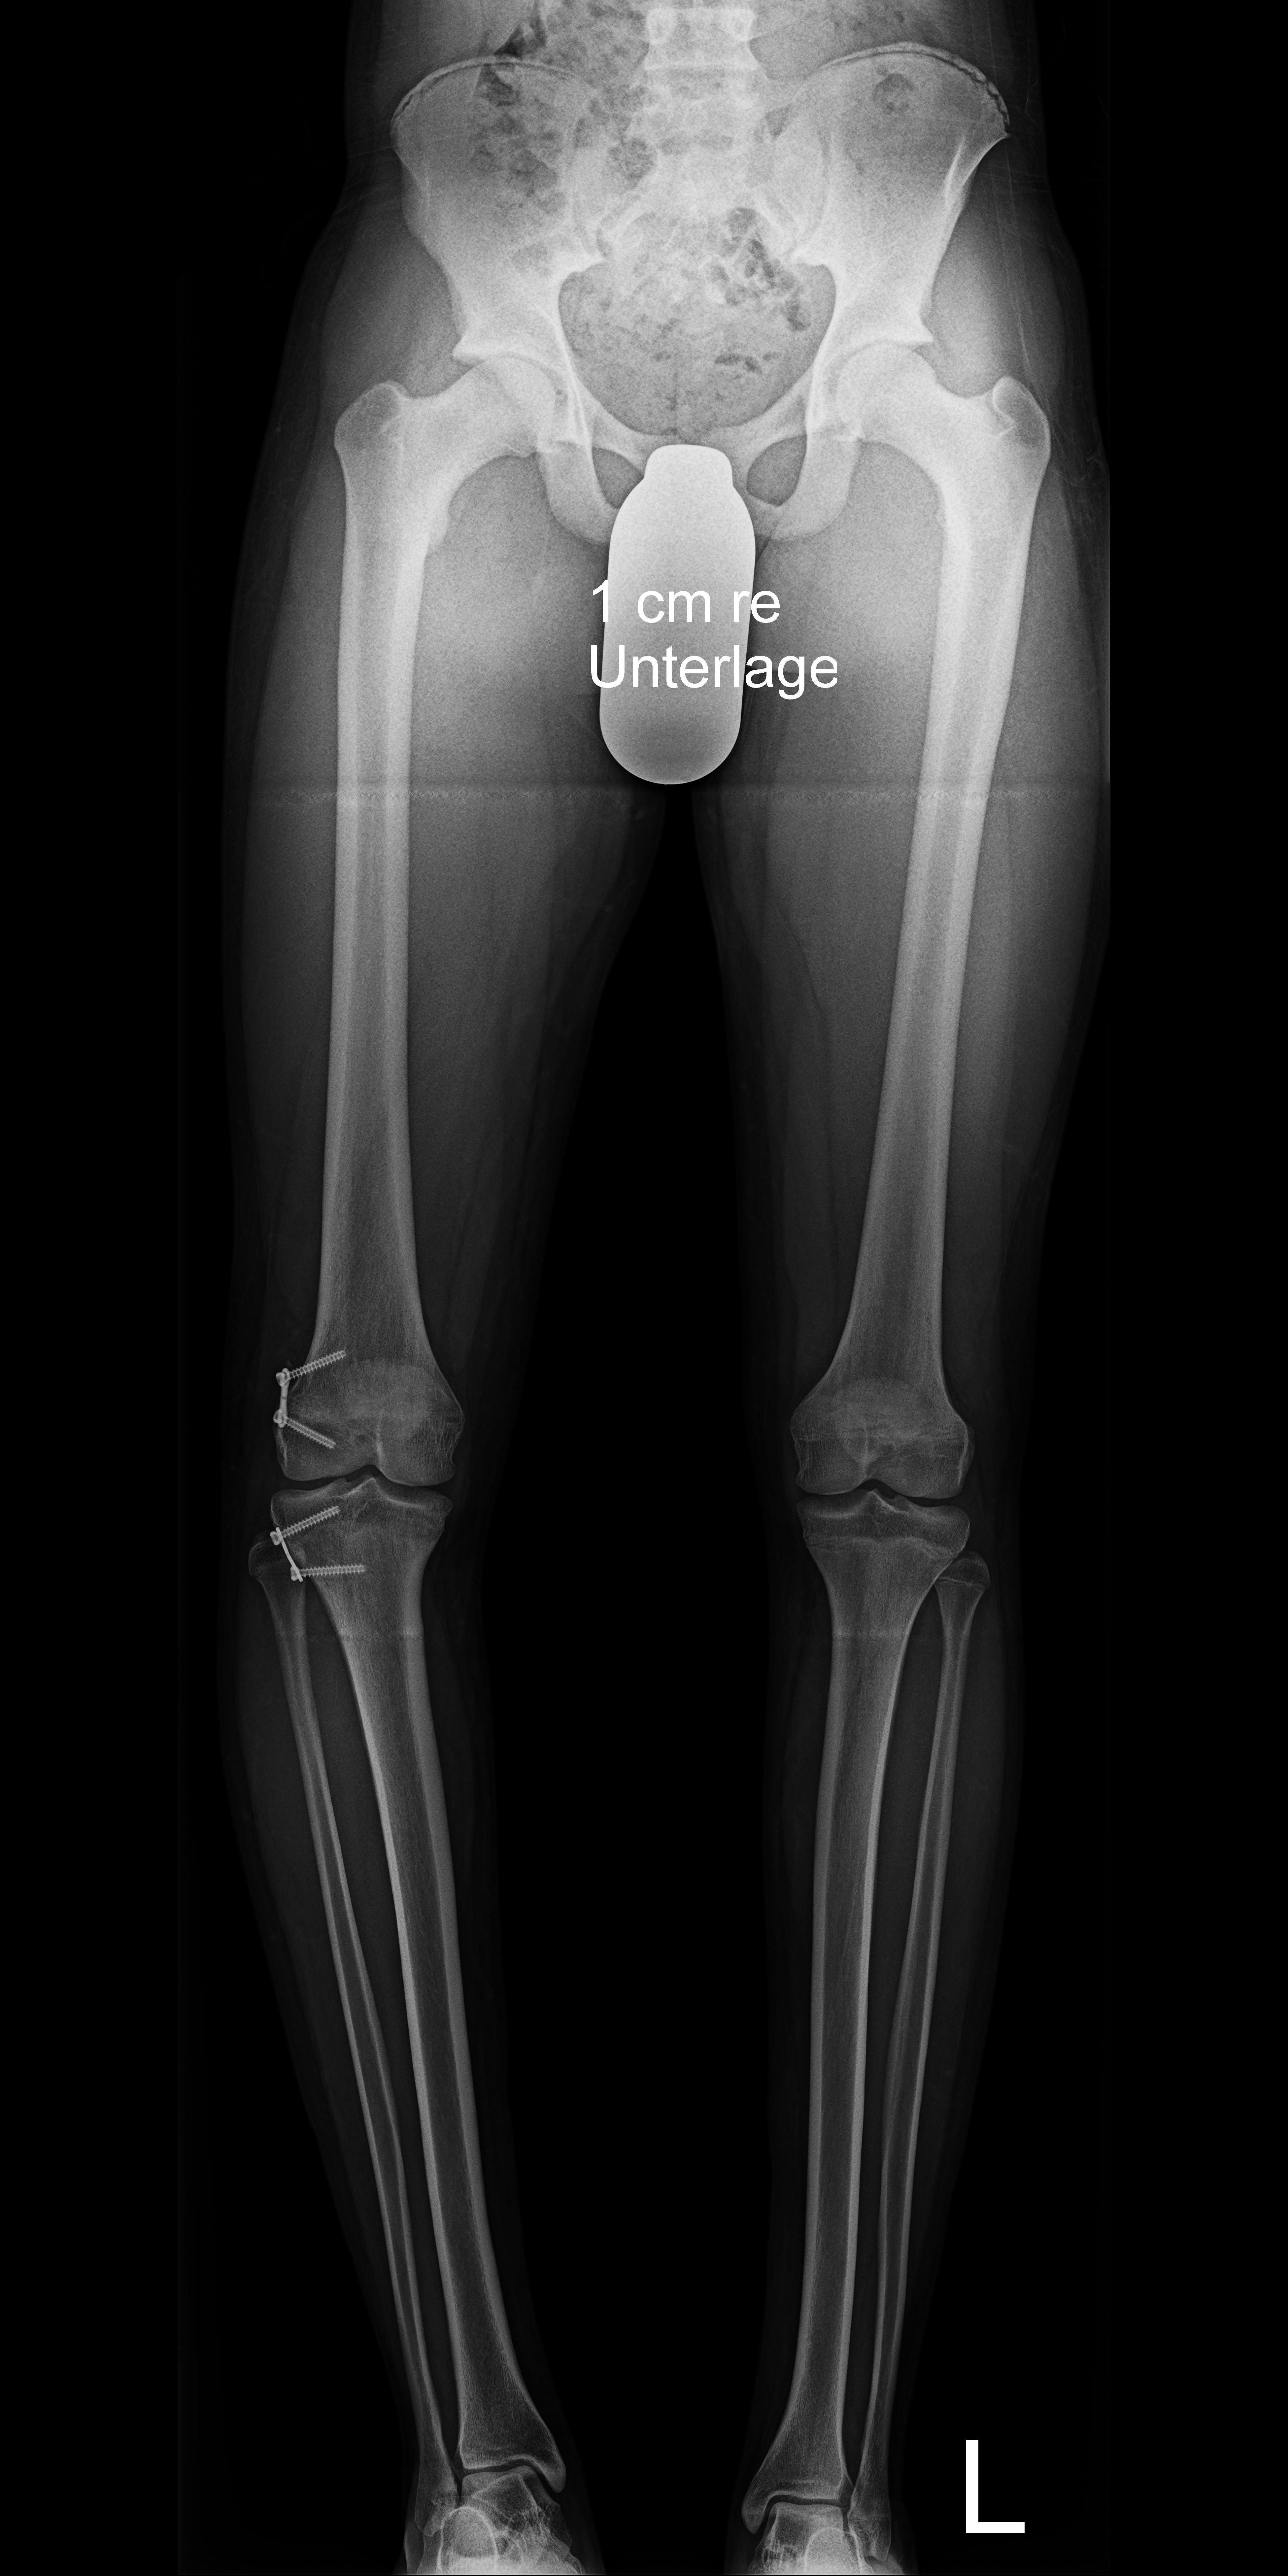

Болезнь Блаунта Фото 115 фотографий